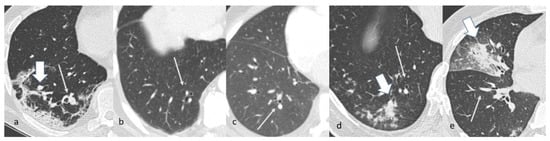

The V/B ratio of the segmental branches of the healthy lung parenchyma in the COV-P group was significantly higher than those of all the other groups (p < 0.0001; Table 1, Figure 2 and Figure 3). The V/B ratio of the subsegmental branches of the healthy lung parenchyma in the COV-P group was the highest among the groups and significantly higher than those of the NL, DTE, and Fung-P groups (p ≤ 0.0001; Table 1, Figure 4).

When analyzing the measurements of the segmental V/B ratios in patients in the COV-P, Bact-P, and Fung-P groups in the area of lung opacification, the values of group COV-P were always significantly higher than the corresponding values of the two other groups (Table 2, Figure 3 and Figure 5).

Figure 3. Chest CT images of patients in, respectively, group COV-P (a), NL (b), DTE (c), Bact-P (d), and Fung-P (e). Note the segmental branches of the pulmonary artery and the corresponding bronchus on the healthy parenchyma (thin arrows (ae)) and the area of lung opacification (wide arrows (a,d,e)).